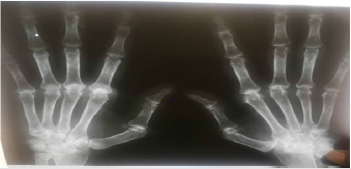

His family history was unremarkable. At the time of presentation, the patient was on Amaryl 4 mg, proton pump inhibitor, prednisolone 5mg and calcicare dietary supplement. On examination, the patient looked unwell, his blood pressure was 120\70. Cardiovascular examination revealed murmur in the apex radiating to the axilla. The examination findings of the respiratory, abdominal and nervous systems were normal. Hand examination had detected bilateral MCP joints swelling, ulnar deviation at wrist joints and fingers, Z shape deformity of thumbs, swan neck deformity of little fingers and visible wasting of thinner muscles. However, there were no tenderness as well as skin and nail changes. All the previously mentioned hand deformities were correctable. Radiological examination of the hands showed ulnar deviation that is more prominent in the metacarpophalangeal joints and marked joint subluxation in both thumbs.

Figure 1: (A) hands showing ulnar deviation of Metacarpophalangeal joints of both hands with swelling, (B) Hand shows correctable joint deformity.

Figure 3: the figure shows the ulnar deviation in the MCP joints and thumbs sublaxation with apparent soft tissue swelling and signs of osteopenia.